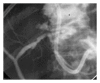

Bile leaks from the intrahepatic biliary tree are an important cause of morbidity following hepatic surgery and trauma. Despite reduction in mortality for hepatic surgery in the last 2 decades, bile leaks rates have not changed significantly. In addition to posted operative bile leaks, leaks may occur following drainage of liver abscess and tumor ablation. Most bile leaks from the intrahepatic biliary tree are transient and managed conservatively by drainage alone or endoscopic biliary decompression. Selected cases may require reoperation and enteric drainage or liver resection for management.